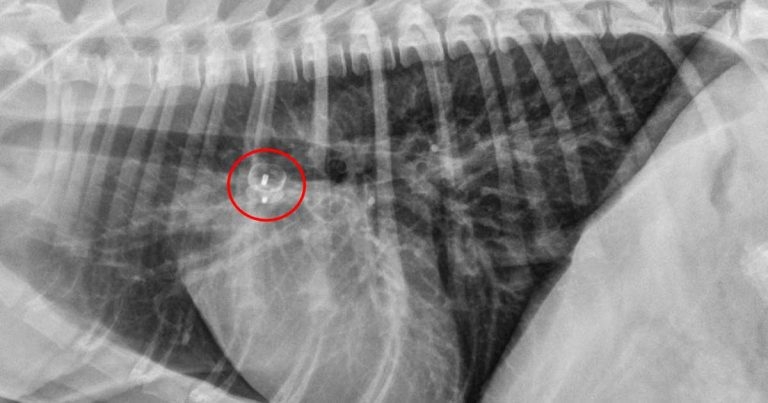

Cardiology specialists are trained to perform some interventions to correct life‑threatening congenital defects, either surgically or via catheterisation using minimally invasive procedures (Figures 1a and 1b).

Thoracotomy and surgical ligation, in the hands of an experienced surgeon, is a well‑established and successful method for PDA closure in dogs. However, minimally invasive per-catheter procedures (canine duct occluder technique) have demonstrated a similar success rate and a more rapid recovery1.